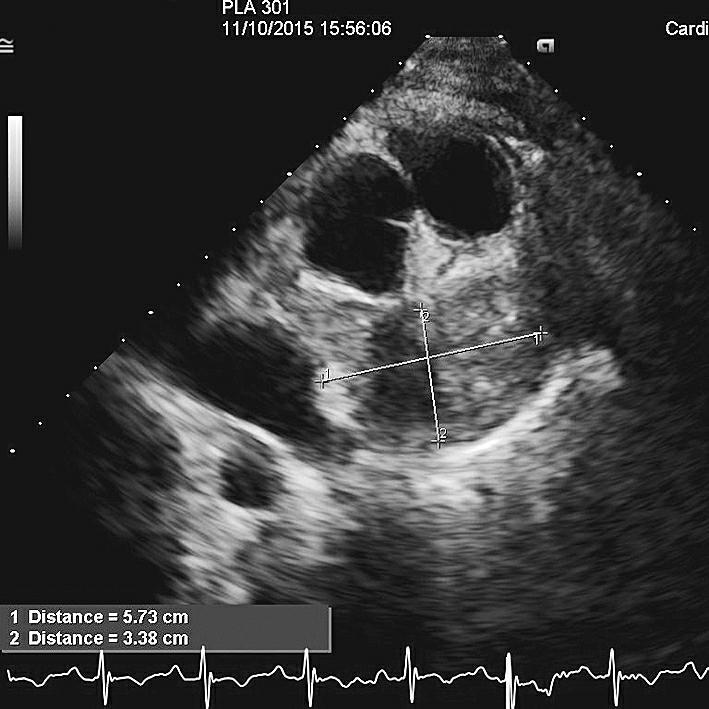

随访结果:患者于肿瘤科接受化疗,经2个周期(每7天1个周期)后,再次行超声心动图检查,结果是肿瘤体积缩小,为5.7cm×3.4cm,同时未见明显心包积液(图6)。

图6化疗后超声心动图